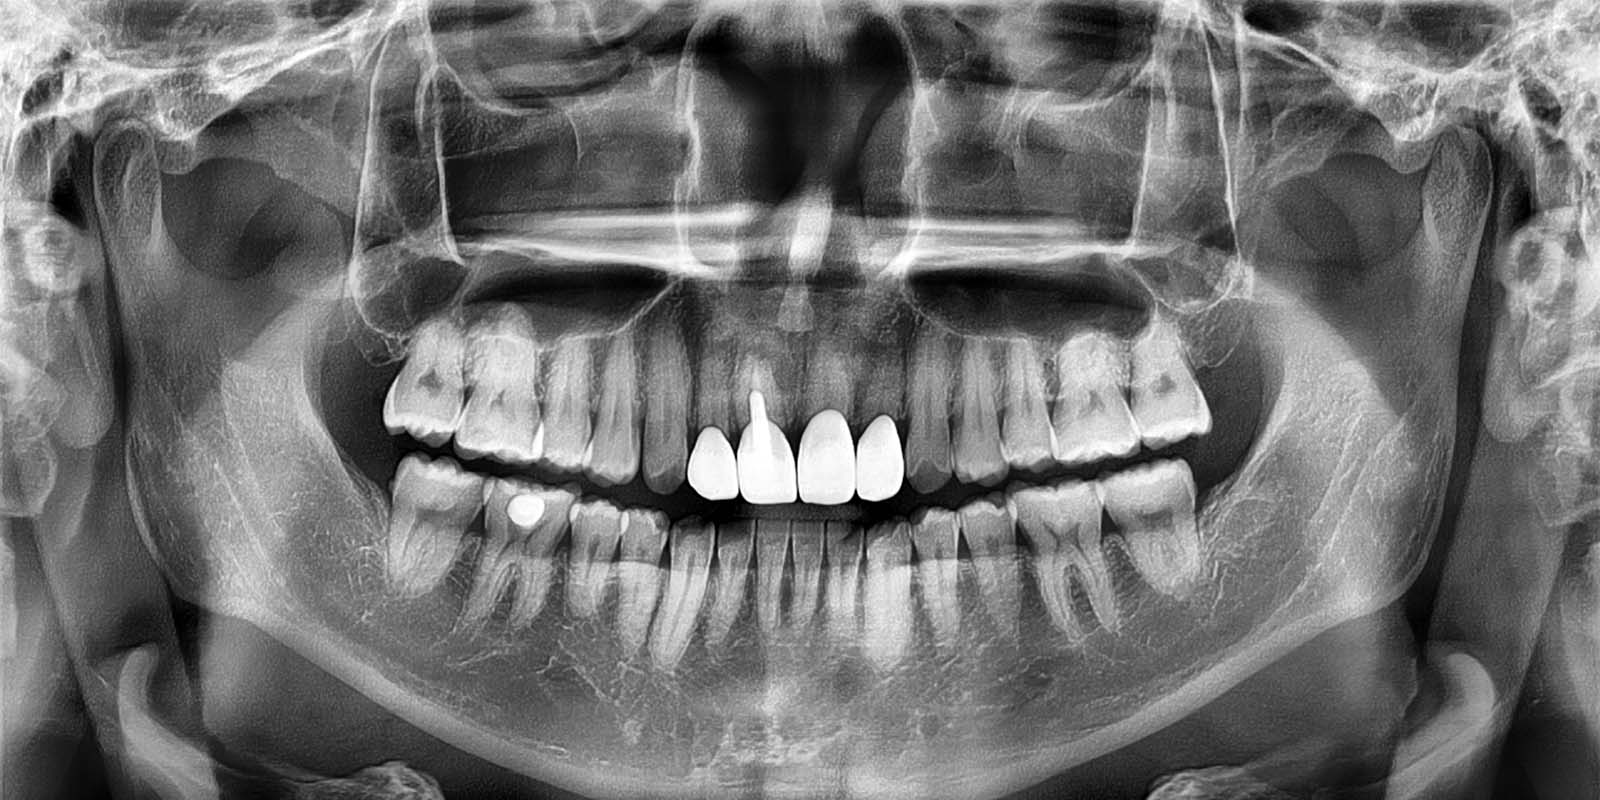

파노라마 사진. 잇몸 속 치아 사진을 한 눈에 확인합니다.

파노라마 엑스레이는 전체 치아 상태를 평면으로 확인하는 데 사용됩니다. 초진 시 환자분의 치아 상태를 전체적으로 파악하기 위해 촬영을 권장합니다. 건강보험이 적용되어 비용은 1만원 내외입니다.

전체 치아, 턱뼈, 상악동 등 넓은 범위를 한 장의 2차원 사진으로 촬영합니다. 전체적인 구강 상태를 한눈에 파악할 수 있어 처음 내원하신 환자분의 전반적인 검진에 주로 활용됩니다.